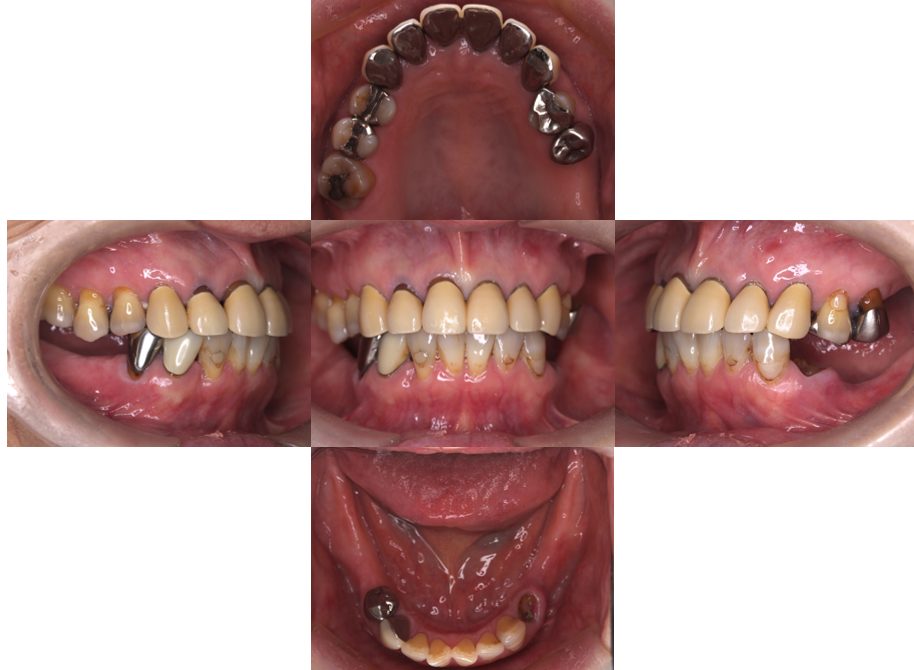

| 主訴 | 60代女性 他院で義歯を作ったが噛みにくい、バネを掛けている左下の銀歯が何度も取れる、しっかり噛めるようになりたい |

| 治療内容 | 歯周病組織再生療法、インプラント治療、セラミック治療を行いました。 |

| 治療費 | 4,000,000円(税込み) |

| 治療期間 | 1年半 |

| 治療回数 | 25回 |

| 想定されたリスク | 失活歯が多く、太くて長い土台がすでに入っていたので、歯根破折のリスクがあった |